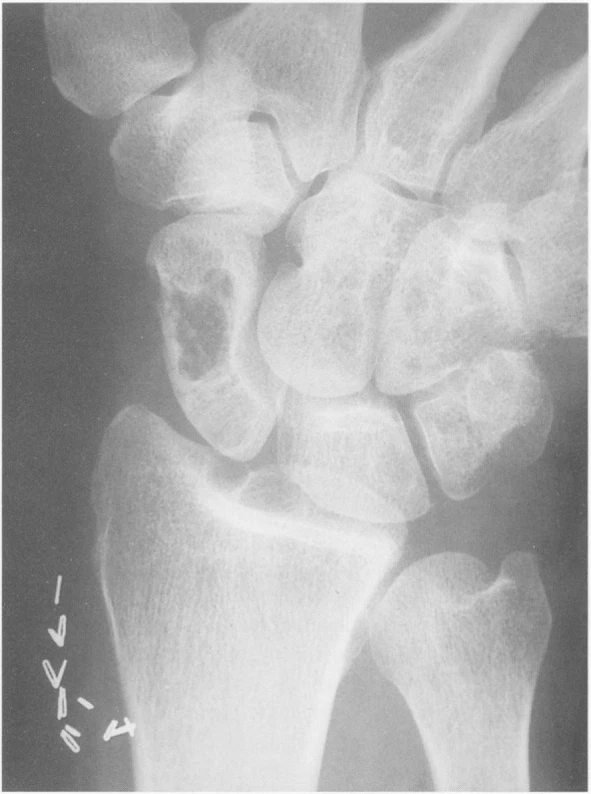

Рентгенография скелета: характерно выявление кист в головках бедренных костей, плечевых костях, надколенниках, вертлужных впадинах и позвоночнике[6].

Компьютерная томография скелета: позволяет идентифицировать псевдоопухолевые образования и псевдокистозные участки в околосуставной костной ткани. Кроме того, томография является наиболее эффективным методом для обнаружения небольших зон остеолиза в кортикальном слое кости или костной эрозии и может быть полезной для оценки распределения и масштабов деструктивных изменений[5].